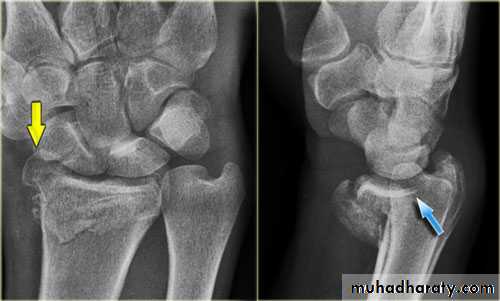

Fall on out stretched hand

xray